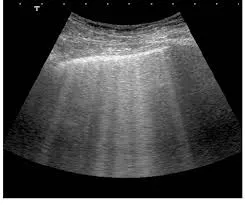

* Redução de massa muscular (evidenciada por imagem e circunferência do braço)

* Redução da massa muscular, avaliada por circunferência muscular do braço ou exames de imagem.